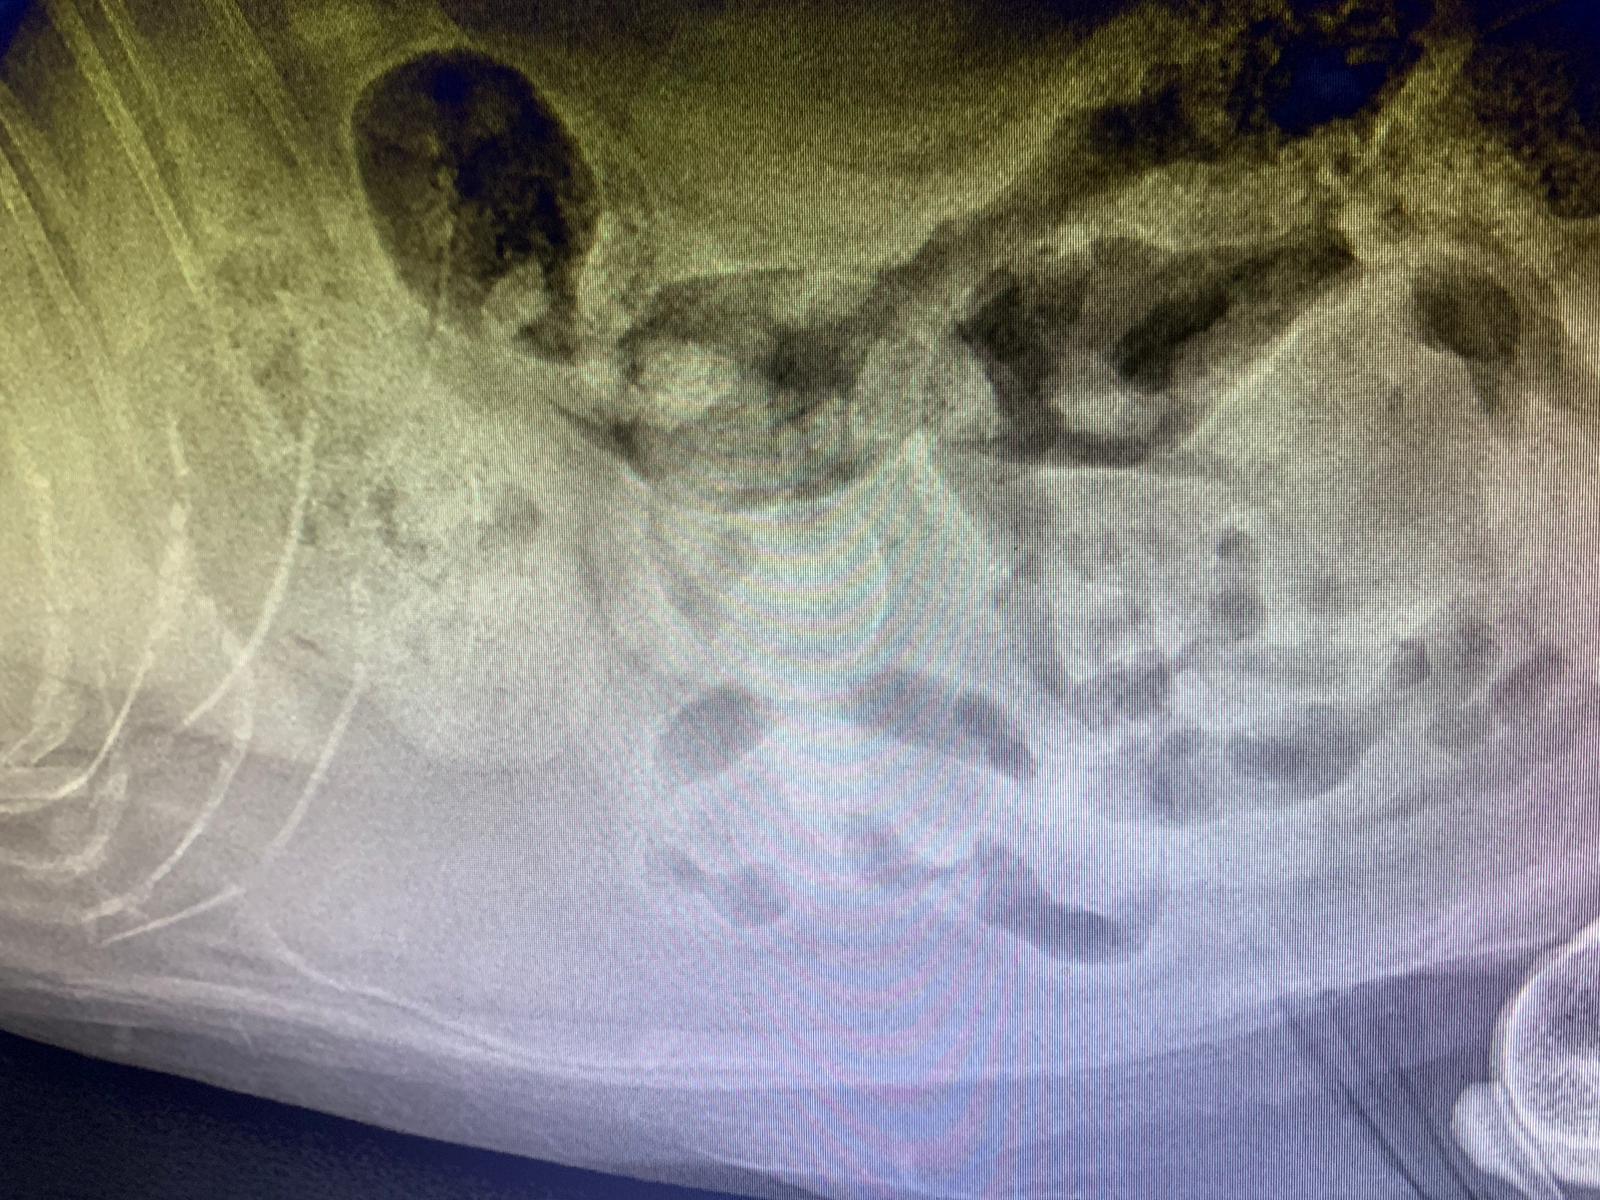

Dr nally says don’t like the muffed sound of his lung, noisy, i scare got fluid ah. Taken X-ray.

X-ray show he got one lump of fluid on the left, cannot confirm what it is. Unless abdominal u/s – I rather spend money on bupre.

His lower spine one part should be in pain.